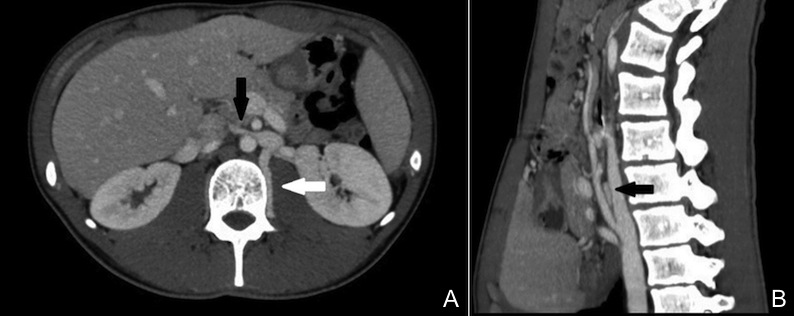

Durante il ricovero il ragazzo si mantiene in buone condizioni generali, il monitoraggio della pressione arteriosa mostra valori normali. Il peso rimane stabile e la diuresi buona. Il dosaggio delle proteine sulle urine mostra una proteinuria di 4 g nelle 24 ore. Curiosamente, fin dallesordio, il ragazzo emette incostantemente urine molto scure alternate a urine chiare rosate. Ci troviamo quindi di fronte a unematuria macroscopica accompagnata da proteinuria in range nefrosico ma senza segni clinici e laboratoristici di sindrome nefrosica. Questo quadro clinico, associato al dato di unematuria macroscopica molto variabile nella sua entità anche nellarco della stessa giornata, ci induce a ipotizzare una sindrome nutcracker (o dello schiaccianoci). La TC addome conferma il sospetto diagnostico evidenziando un restringimento della vena renale sinistra in corrispondenza del compasso aorto-mesenterico con relativa ectasia del vaso a monte e significativa dilatazione della vena lombare omolaterale (Figura 1). Nei giorni successivi lematuria e la proteinuria si risolvono progressivamente e spontaneamente. A distanza di 5 mesi il ragazzo non ha più presentato sintomi.

La sindrome nutcracker - o dello schiaccianoci - consiste nella compressione della vena renale sinistra tra laorta e larteria mesenterica superiore con conseguente aumento della pressione venosa renale e rottura delle piccole vene renali con stravaso di sangue nel sistema collettore.